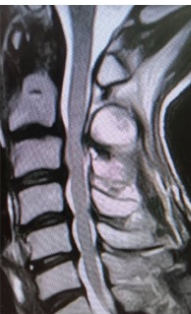

A Clinical Experience in Treating Myelopathy Caused by Floating Lamina Resulting from Re-close of the Lamina and Pseudarthrosis at the Lateral Gutter after Cervical Laminoplasty

Arihiko Tsukamoto , Takashi Osima , Shutaro Fujimoto , Tomonori Morita , Atsushi Teramoto

………………………………p.323-328